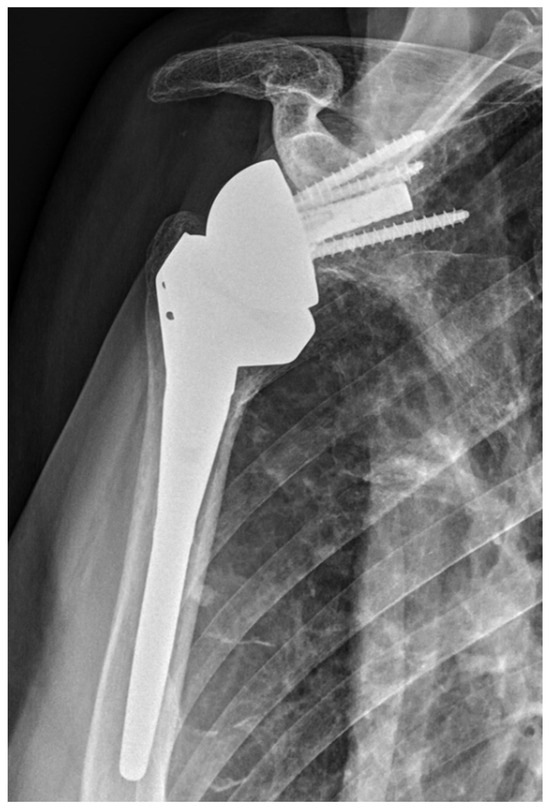

2.2. Surgical Procedure